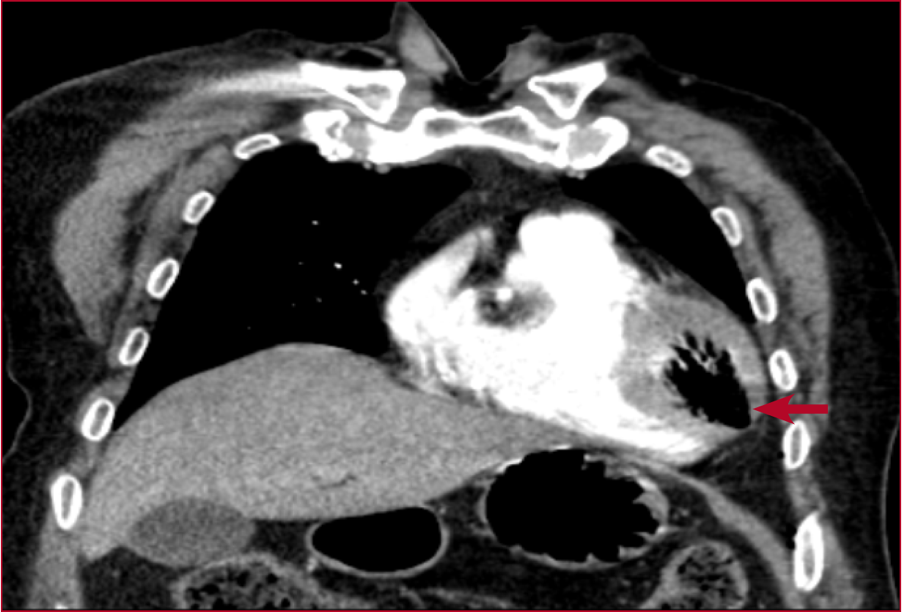

Figura 2. Tomografía computarizada de tórax

con contraste intravenoso, corte coronal a nivel toracoabdominal superior. Se

visualiza una embolia aérea en el ventrículo izquierdo (flecha) después de la

punción-aspiración pulmonar.